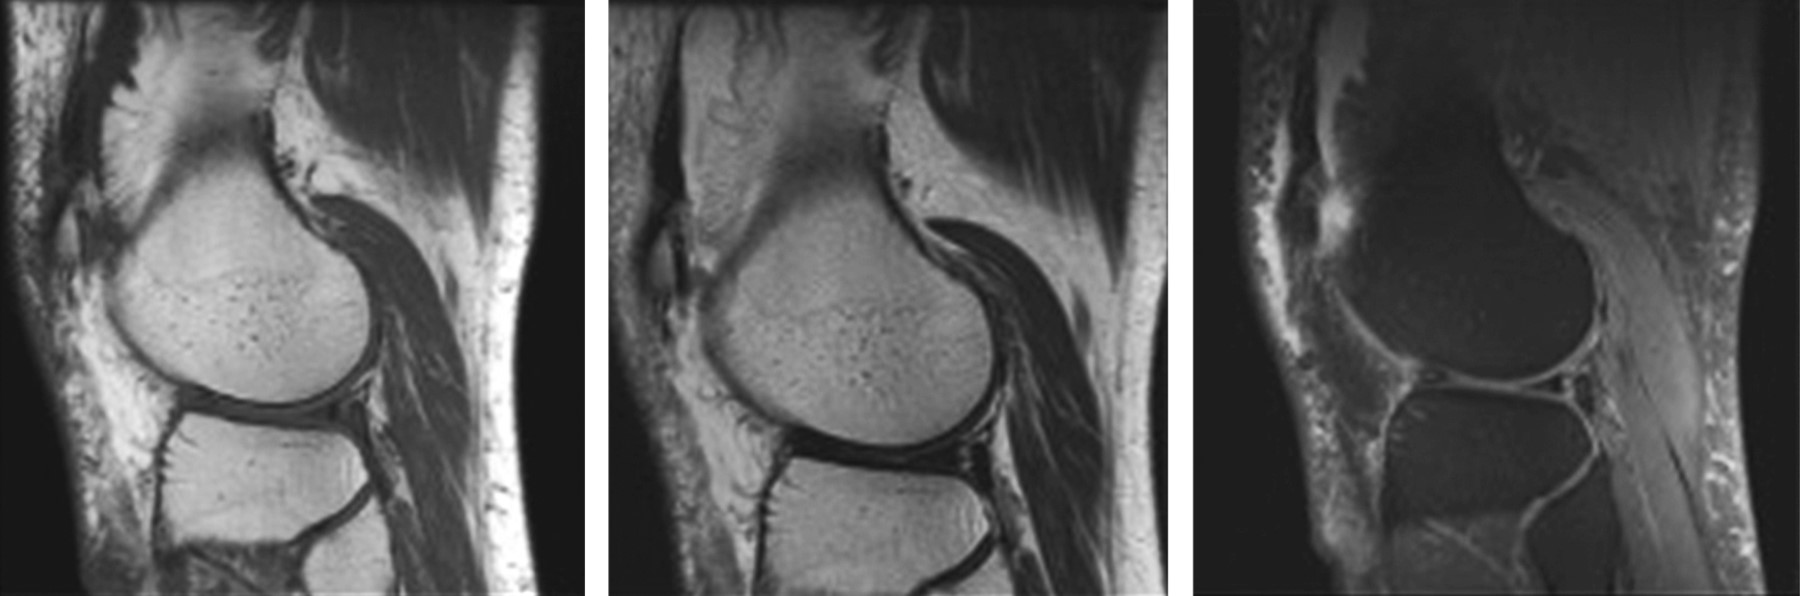

Arborescente lipoma by magnetic resonance imaging

Synovial lipomatosis is a rare entity of the synovial membrane. It most frequently affects the knee joint but may also occur in other joints. It occurs in men in the fifth or sixth decade of life, with a usual monoarticular presentation. Its etiology is unknown, but a reactive rather than neoplastic process is supported. This disease has a characteristically arborescent radiological, macroscopic, and microscopic morphology due to adipose infiltration of the sub-synovial tissue, which is key for its diagnosis.

Figure 1